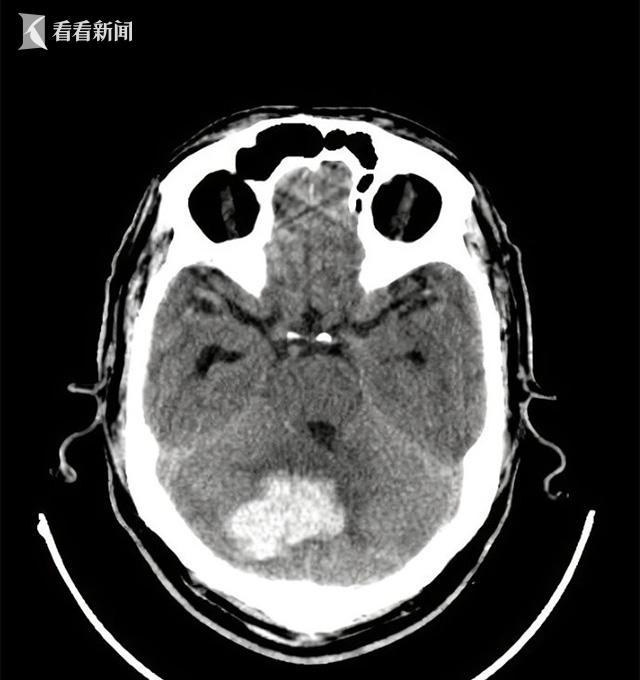

6. 脑出血

脑干、小脑、四脑室的脑出血也可表现为急性出现的眩晕发作,但往往同时伴有剧烈头痛、恶心、呕吐、肢体瘫痪、血压增高,常常很快就会进展意识不清、昏迷。导致脑出血最常见的原因是没有得到有效控制的高血压、脑动脉瘤、脑动静脉畸形等。

头颅影像学的检查(包括头颅CT与磁共振)是十分必要和紧迫的,因为我们需要快速排查急性眩晕是否是由于脑梗死或脑出血这种可危及生命的疾病引起。头颅CT可快速发现是否存在脑出血,但对发病时间很短(

脑干、小脑或四脑室的出血病情十分危重,需要进行外科手术清除血肿。即便如此,此类疾病也常常预后不佳,最终演变成持续植物状态或脑死亡也不少见。